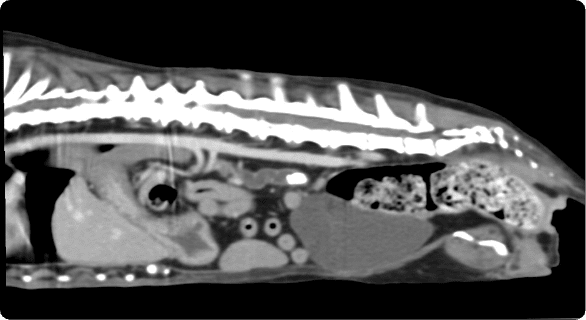

일산시티동물의료센터 영상의학센터는 최첨단 장비를 기반으로, 반려동물의 건강 상태를 보다 정확하고 신속하게

진단하는 핵심센터입니다. 고화질 CT와 초음파, 디지털 엑스레이, 투시촬영기기(C-arm)을 사용해

고해상도 영상과 정밀한 분석을 통해 질병의 조기 발견과 맞춤 치료 방향 제시를 목표로 합니다.

빠른 촬영속도를 통해 마취시간을 최소화 하며, 선명한 3차원 영상을 구현합니다.

종양, 전이평가, 선천적 혈관 기형 등 여러 질환의 조기 발견 및 환자상태를 평가합니다.

간, 비장, 소화기, 콩팥, 방광, 부신의 종양, 간문맥전신단락, 복강 내 실질 장기 평가, 요로결석에 의한 폐색 평가